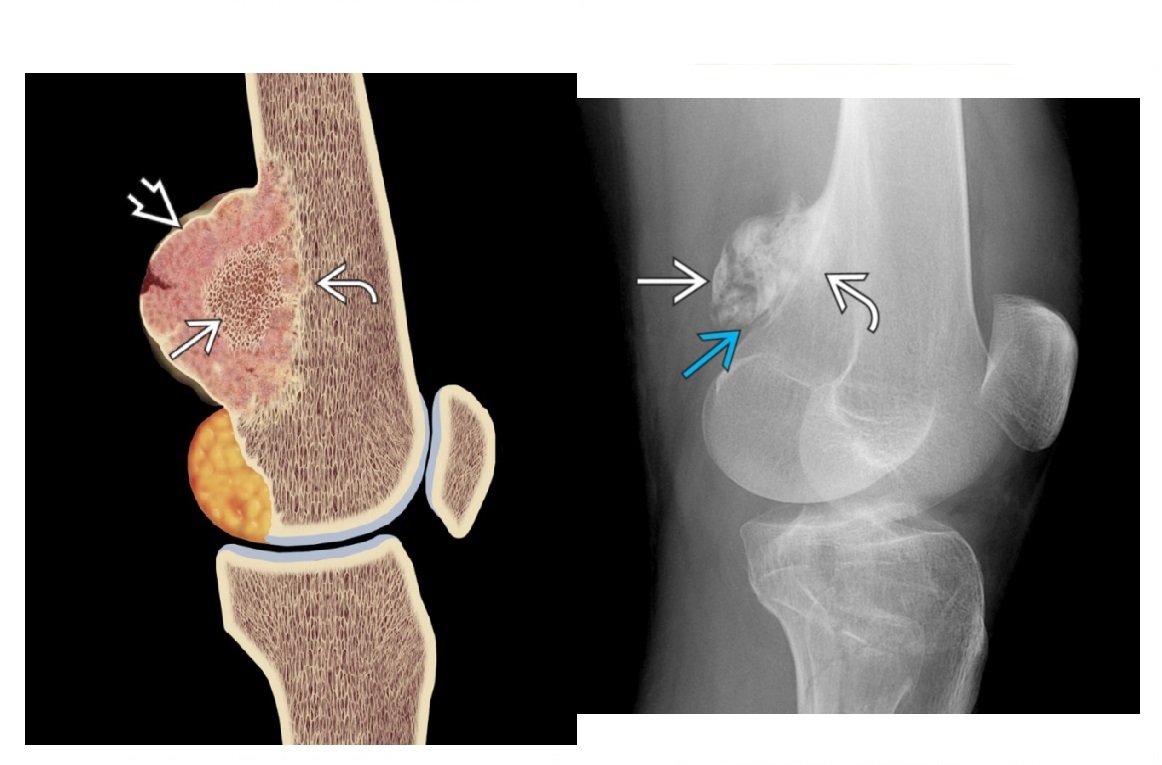

osteosarcoma

Femur (40%) and proximal tibia commonest sites (15%)

**Aggressive periosteal reaction **

- Sunburst

- Codman triangle

- Lamellated (onion skin)

**High grade = Met to the lung

**

Reverse zoning phenomenon - dense mature matrix in the centre, less peripherally